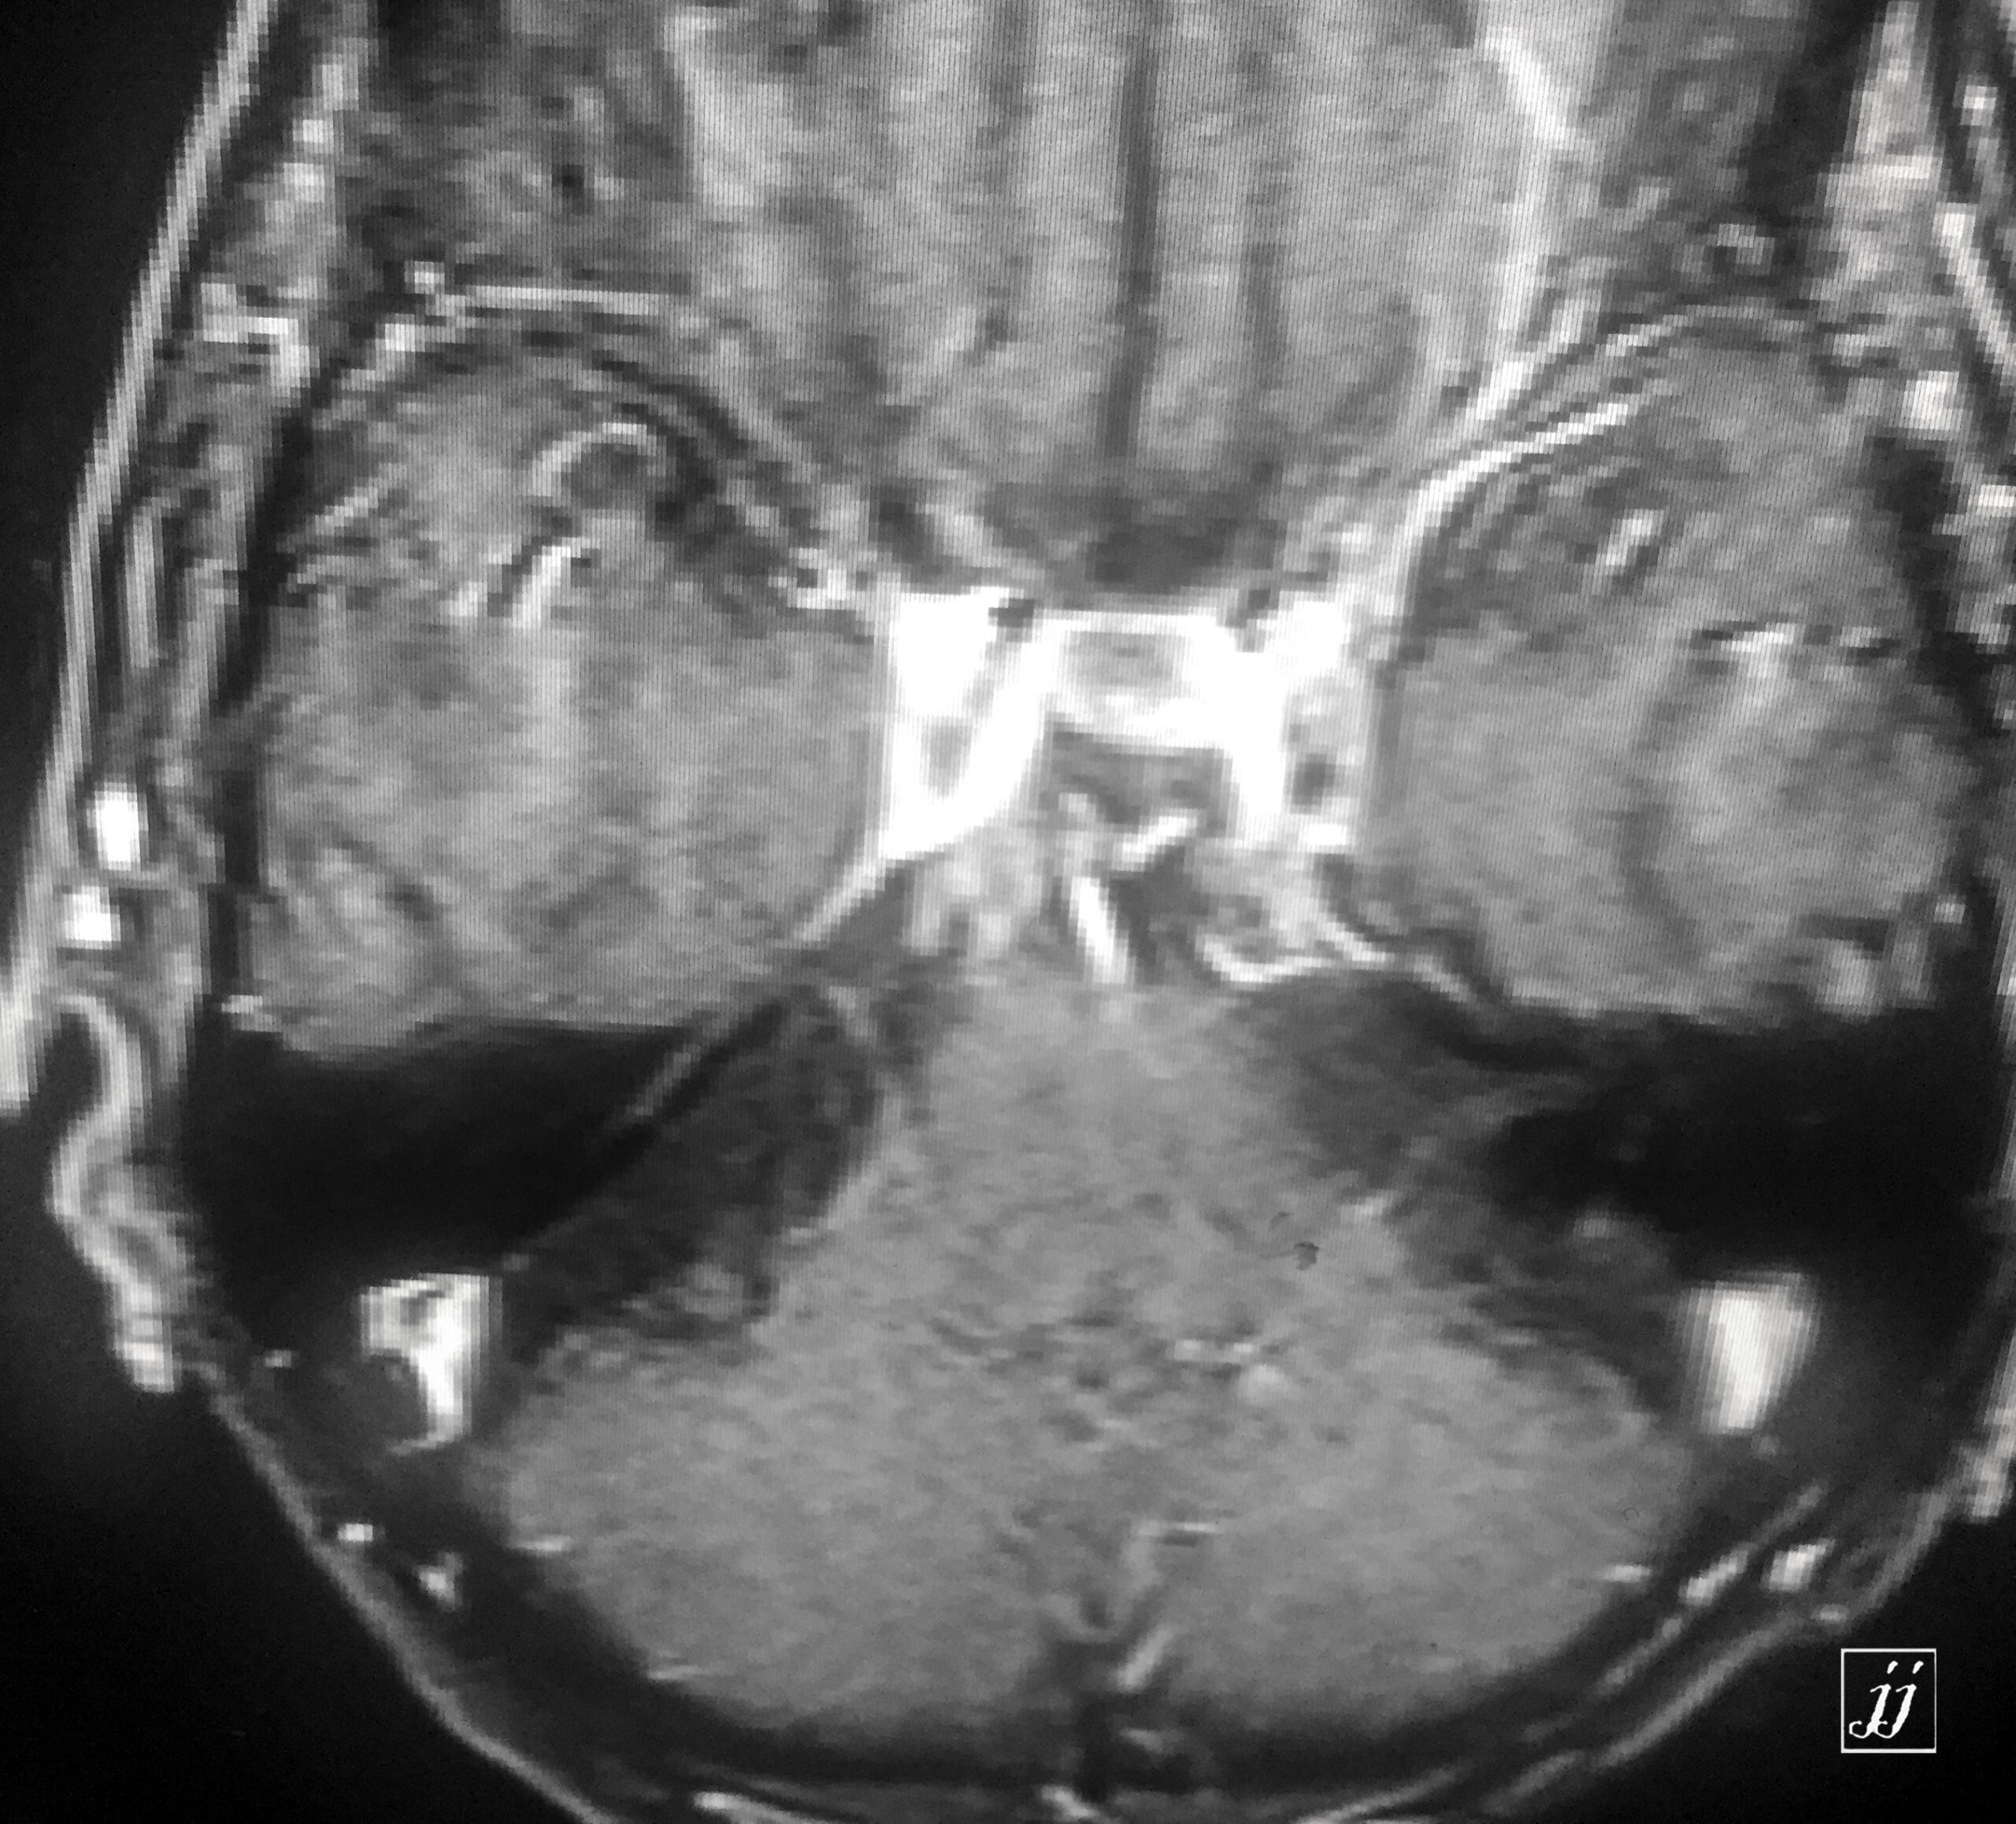

Brain- left mastoid abscess (8)